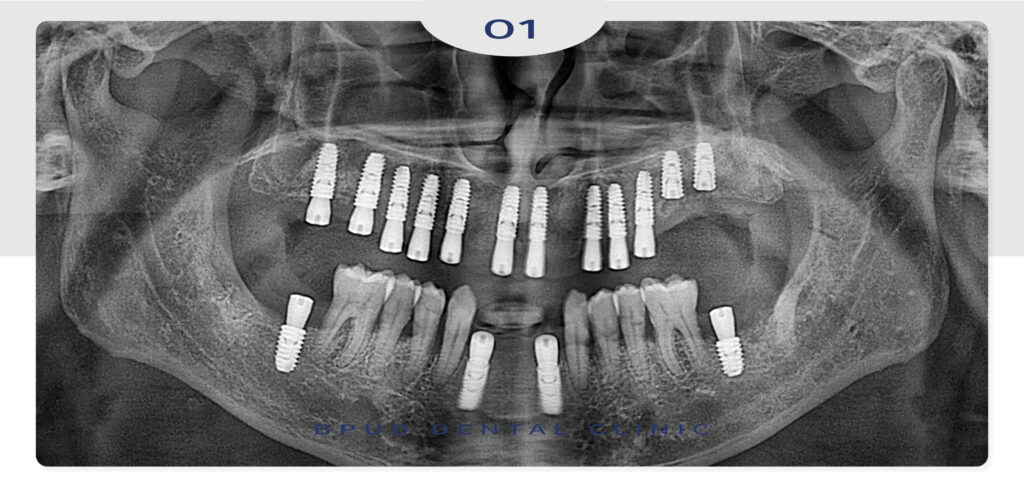

위쪽의 임플란트를 먼저 식립하고

왼쪽 위 어금니 부위는 잔존 치조골이

많이 부족하여 상악동 거상술을 통해

골이식을 먼저 시행한 뒤 추후 식립을

진행하기로 하였습니다.

한달 뒤, 아래 앞니와 어금니 부위도

식립을 하였습니다.

이어서 상악동 거상술을 시행한 지

약 5개월 후 왼쪽 위 임플란트를 식립하였습니다.